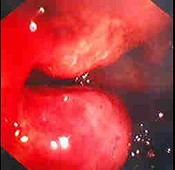

男,35岁,腹痛、腹泻、腹胀、脓血便、里急后重,结合图像,选择最可能诊断( )

A:溃疡性结肠炎

B:结肠克罗恩病

C:结肠结核

D:假膜性肠炎

E:结肠淋巴瘤